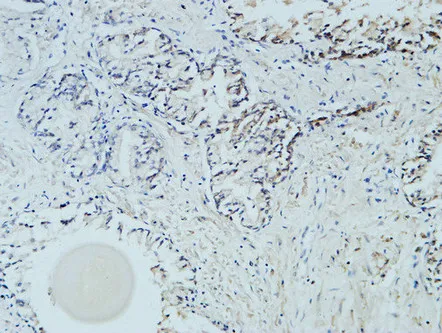

Active Caspase-3(5E1)Mouse Monoclonal Antibody

Cat: AMM06555

Size1:50μL Price1:$128

Size2:100μL Price2:$230

Size3:200μL Price3:$380

Application:IF-P,IF-F,ICC/IF,WB,IP,IHC-P

Reactivity:Human,Mouse,Rat,Chicken

Conjugate:Unconjugated

Optional conjugates: Biotin, FITC (free of charge). See other 26 conjugates.

Gene Name:CASP3